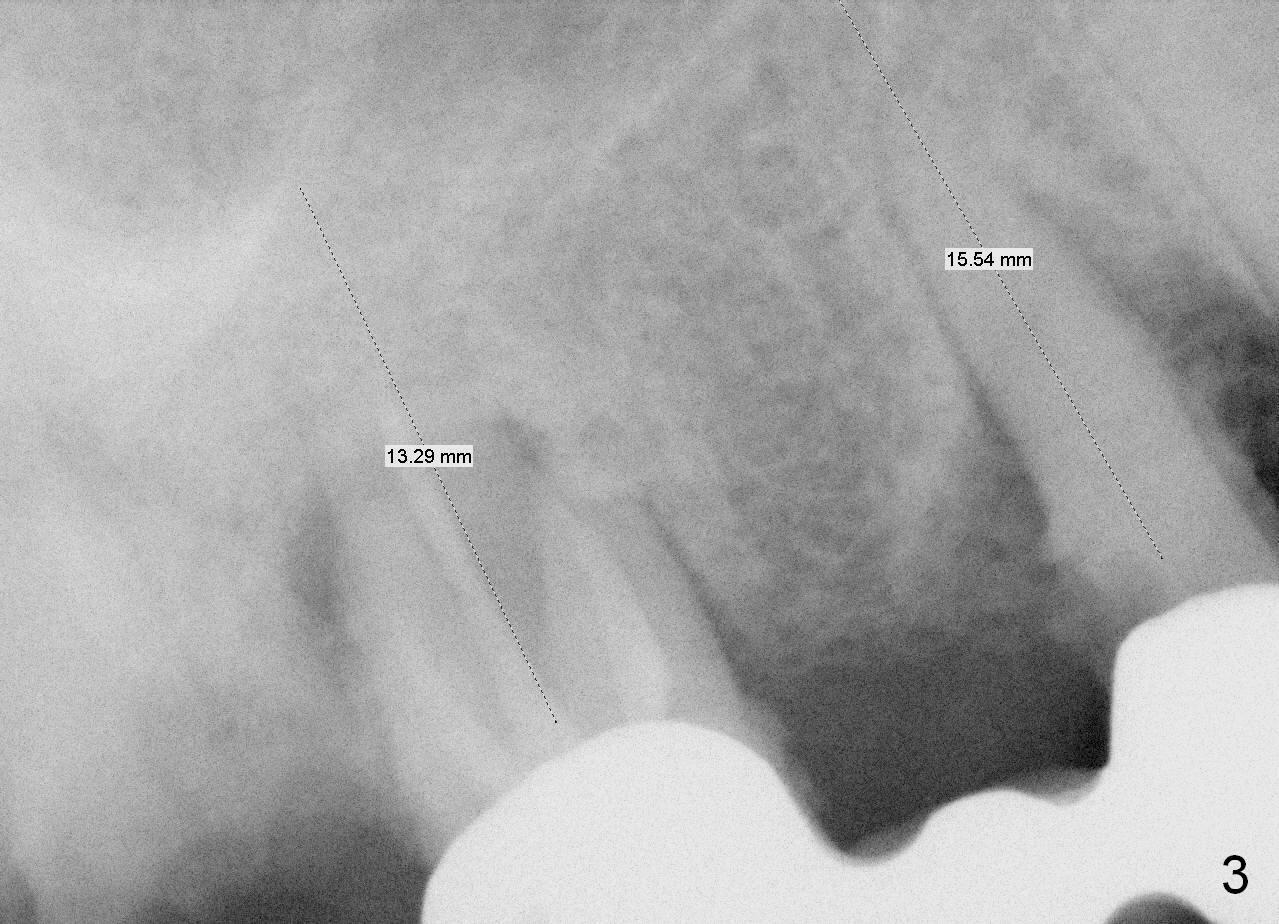

A 78-year-old lady (YT) has had poor dentition. The tooth #2 fractured 3 years ago (Fig.1). Now bone loss around the abutments for the bridge at #3-5 is more severe (Fig.2). There is an abscess palatal to the tooth #5. After extraction, the socket at #3 should be large (treated with 2% Xylocaine/1:50,000 Epinephrine). An extra wide implant is expected. Since there is more than 12 mm of bone in height (Fig.3), a UF implant is the most appropriate (6, 6.5 or 7x12 mm, Fig.4). The longest extra wide SM implant is 10 mm.